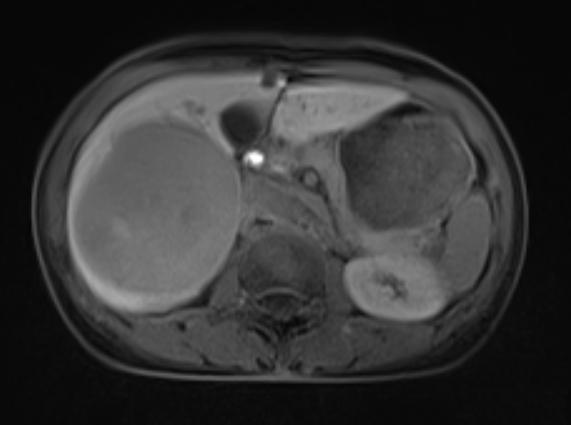

二维CT图

二维MRI图